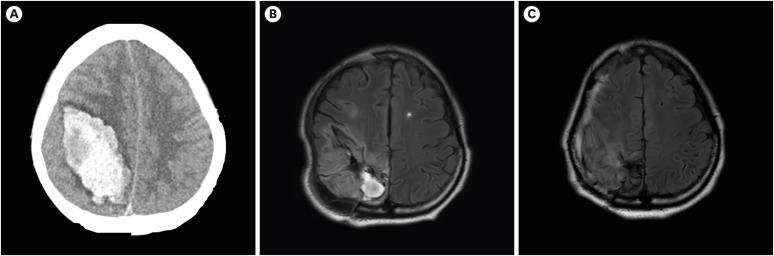

本病例研究描述了一位因颅内出血引起的右侧初级体感觉皮层损伤后出现运动恢复和不自主运动的患者。患者最初出现左臂和左腿麻痹,但后来表现出明显的运动恢复,在恢复过程中伴有多次弹道运动发作。通过弥散张量成像分析研究患者感觉运动相关脑区的变化。与年龄匹配的对照组相比,患者在同病灶红核(RN)中具有更高的分数各向异性和更低的平均扩散系数值。我们假设同侧侧皮质皮质的过度活跃可能在初级体感觉皮质受损后的运动恢复中发挥作用,可能通过其参与感觉运动整合。我们的研究结果表明,在初级体感觉皮层受损后,同侧侧RN可能发生适应性变化。

This case study describes a patient who experienced motor recovery and involuntary movements following damage to the right primary somatosensory cortex caused by an intracranial hemorrhage. The patient initially suffered from paralysis in her left arm and leg, but exhibited significant motor recovery later, accompanied by multiple episodes of ballistic movement during the recovery process. A diffusion tensor imaging analysis was performed to investigate changes in sensorimotor-related brain areas in the patient. The patient had higher fractional anisotropy and lower mean diffusivity values in the ipsilesional red nucleus (RN) than age-matched controls. We assume that hyperactivity of the ipsilesional RN might play a role in motor recovery after damage to the primary somatosensory cortex, potentially through its involvement in sensorimotor integration. Our findings demonstrated the potential for adaptive changes in the ipsilesional RN following damage to the primary somatosensory cortex.